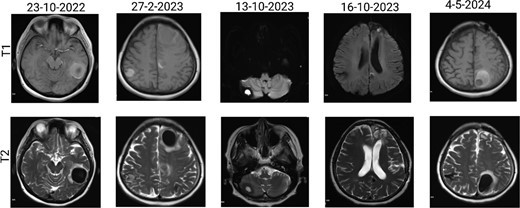

The patient has undergone multiple rounds of MRI and CT (Fig. 3) imaging examinations, the results of which have consistently shown a morphology suggestive of recurrent ICH. T2-weighted (Fig. 4) and susceptibility-weighted (SW) MRI (Fig. 5) showed many cerebral cavernous malformations (CCMs) scattered across both cerebral hemispheres, mainly located in the left parietal, frontal, and occipital lobes, with some lesions extending into the brainstem. Multiple lesions presented with a mixed signal intensity corresponding to different stages of haemorrhage and blood degradation products. There was noticeable hemosiderin deposition, indicating the presence of chronic microhaemorrhages. These deposits were particularly extensive in the left parietal lobe, corresponding to the site of the largest and most symptomatic haemorrhage. Regions of gliosis were observed near the haemorrhagic lesions, indicating long-term damage from previous haemorrhages. SWI confirmed the presence of multiple microhaemorrhagic lesions in the parenchyma and subcortical white matter, complicating the clinical picture.

Brain MRI showing dynamic haemorrhage. (a) T2-weighted MR image showing multiple CCMs. The highlighted portions indicate areas of hemosiderin deposition associated with previous haemorrhages. (b) post-contrast T1-weighted MR images showing the enhancement patterns of CCMs and the extent of the surrounding oedema.